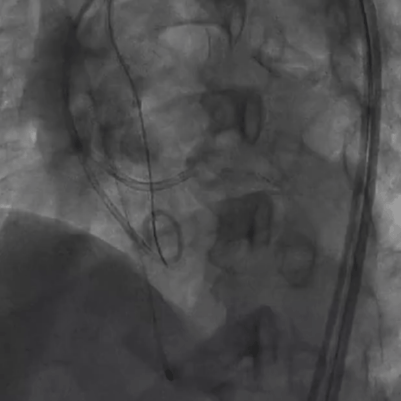

手术过程概览:

主动脉根部造影提示瓦氏窦整体形态偏小,决定给予冠脉保护

导丝左冠保护

导丝跨瓣

18mm球囊预扩,无明显腰征,少许瓣周漏,未见冠脉阻挡,决定选择TaurusOne®AV23瓣膜。

TaurusOne®轻松过弓

TaurusOne®释放过程:

瓣膜定位

瓣膜释放后形态位置良好,造影无返流